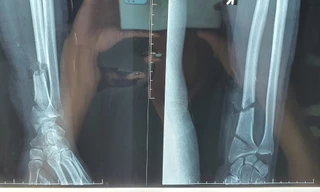

TPO - Trong lúc dùng máy cưa cầm tay để tỉa cây cảnh, một người đàn ông bất ngờ cắt trúng thân cây quá cứng, vô tình máy bị dội ra khiến cổ tay phải bị cắt trúng đứt gần lìa 2 đoạn. Sau đó, chiếc máy rớt còn xuống đất trúng cổ chân 2 bên, bệnh nhân phải nhập viện trong tình trạng vô cùng nguy kịch.